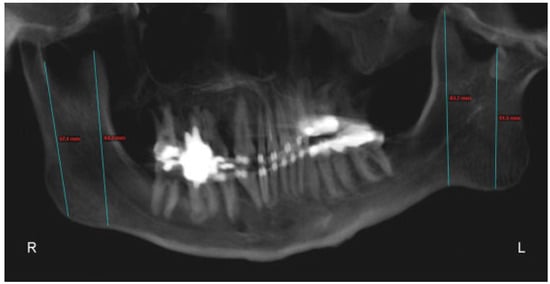

:Case Report